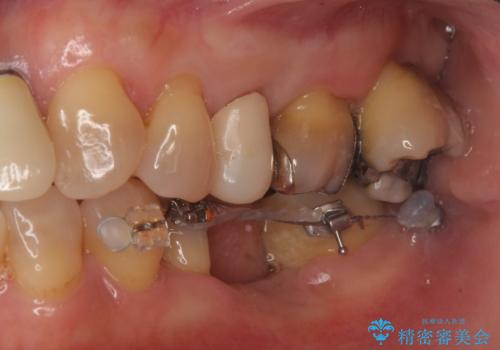

インプラントではなくブリッジにするためには、奥歯の並びを矯正しておいた方がいい状態でした。

抜歯後に部分的にワイヤー矯正を半年ほど行ってから、ブリッジを入れる治療を行いました。